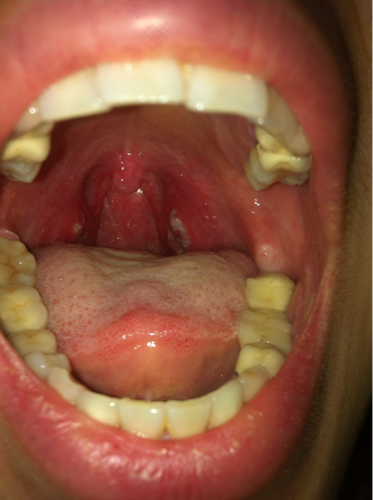

咽喉部化脓性感染,多见于化脓性扁桃腺炎,检查可见增到扁桃体表面覆有脓胎,可出现咽痛,发热,咳嗽,倦怠,食欲不振等症,需要积极抗炎治疗。

咽喉化脓伴有疼痛明显,或者发热的,应该是咽部急性炎症,如急性扁桃体炎等。应该使用抗生素进行治疗。如果无痛,无自觉症状的,或者仅有咽异物感,可能是咽角化症等可以不必治疗。